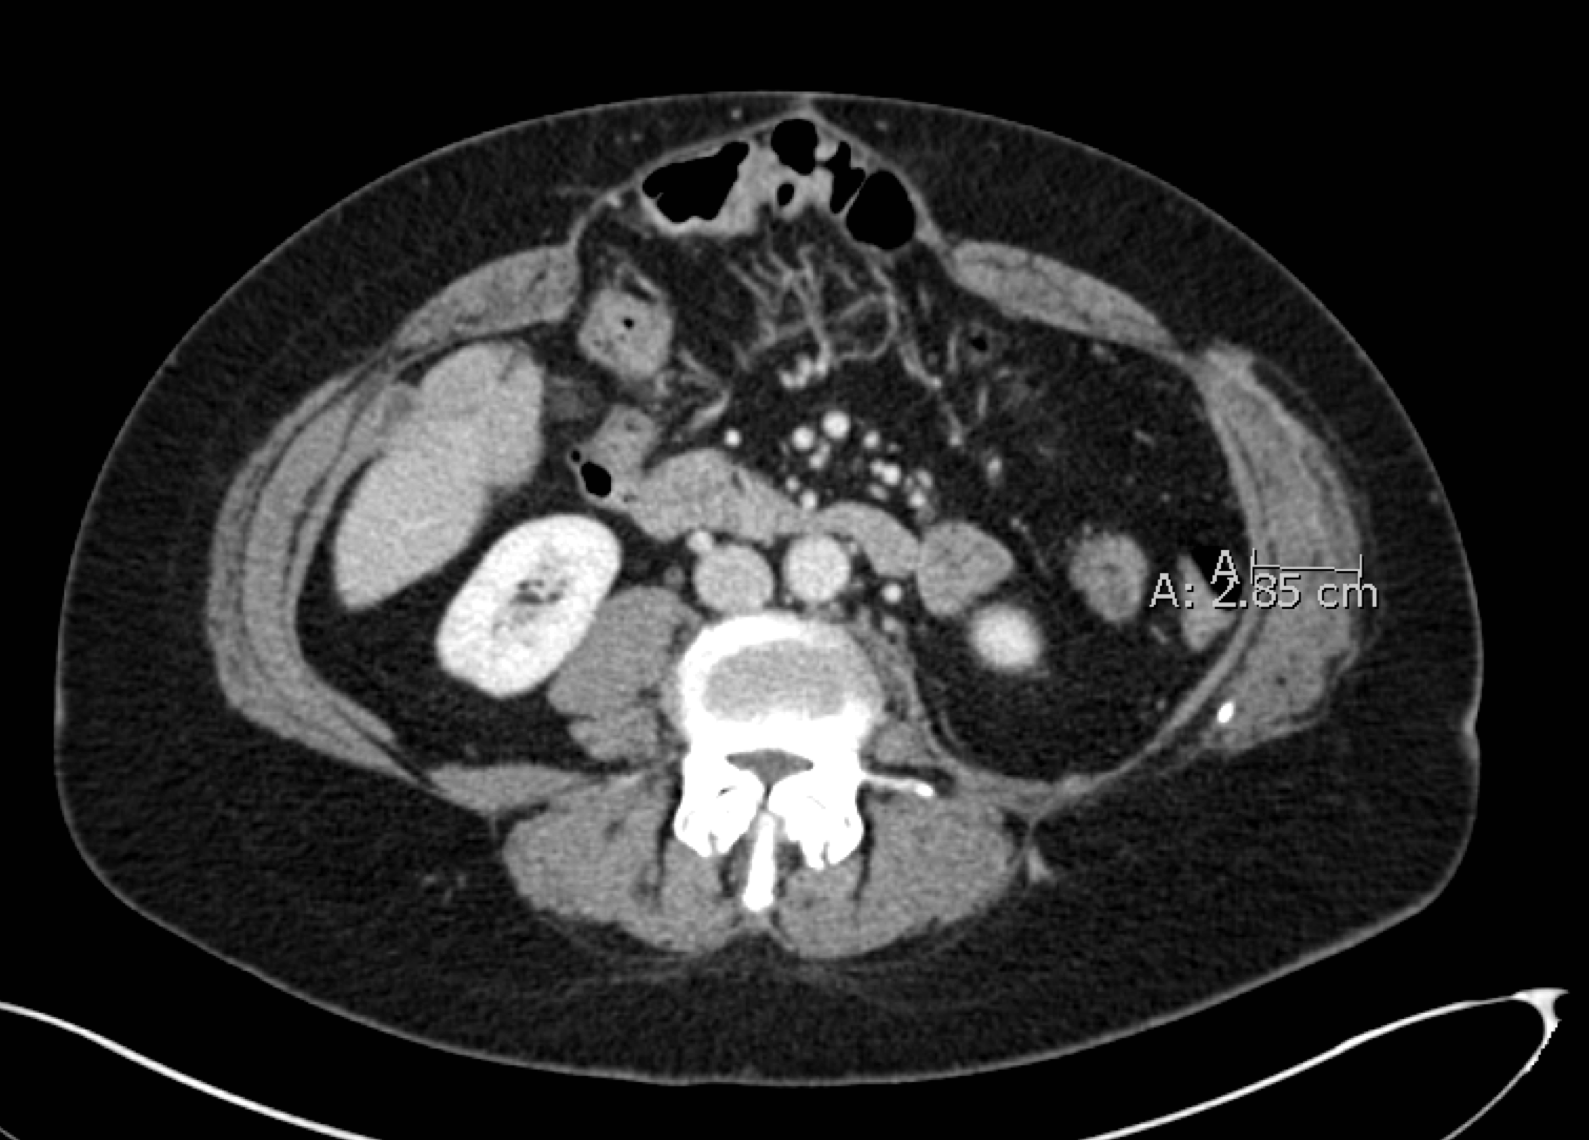

These CT scans of a cross-section of Goff's abdomen show how the Botox enabled Eriksson to pull her abdominal muscles back into position. At top, pre-surgery, the hernia is visible at the top of the scan. A measurement shows the right abdominal muscle has retracted and, as a consequence, has thickened to a width 2.85 cm. In the lower image, the muscle has been stretched thinner, so the new measured width is 1.82 cm, and pulled back to the center of her body. Images provided